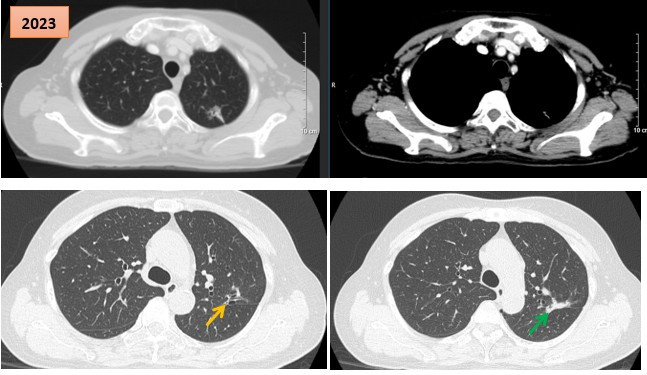

Đau bụng kéo dài bệnh nhân được phát hiện mắc cùng lúc 2 ung thư nguyên phát

Thứ Hai, ngày 20/04/2026 15:32Từ một ca đau bụng kéo dài, bác sĩ phát hiện bệnh nhân mắc đồng thời ung thư đại tràng và ung thư phổi nguyên phát. Ca phẫu thuật kéo dài 4,5 giờ được triển khai thành công, giúp bệnh nhân phục...